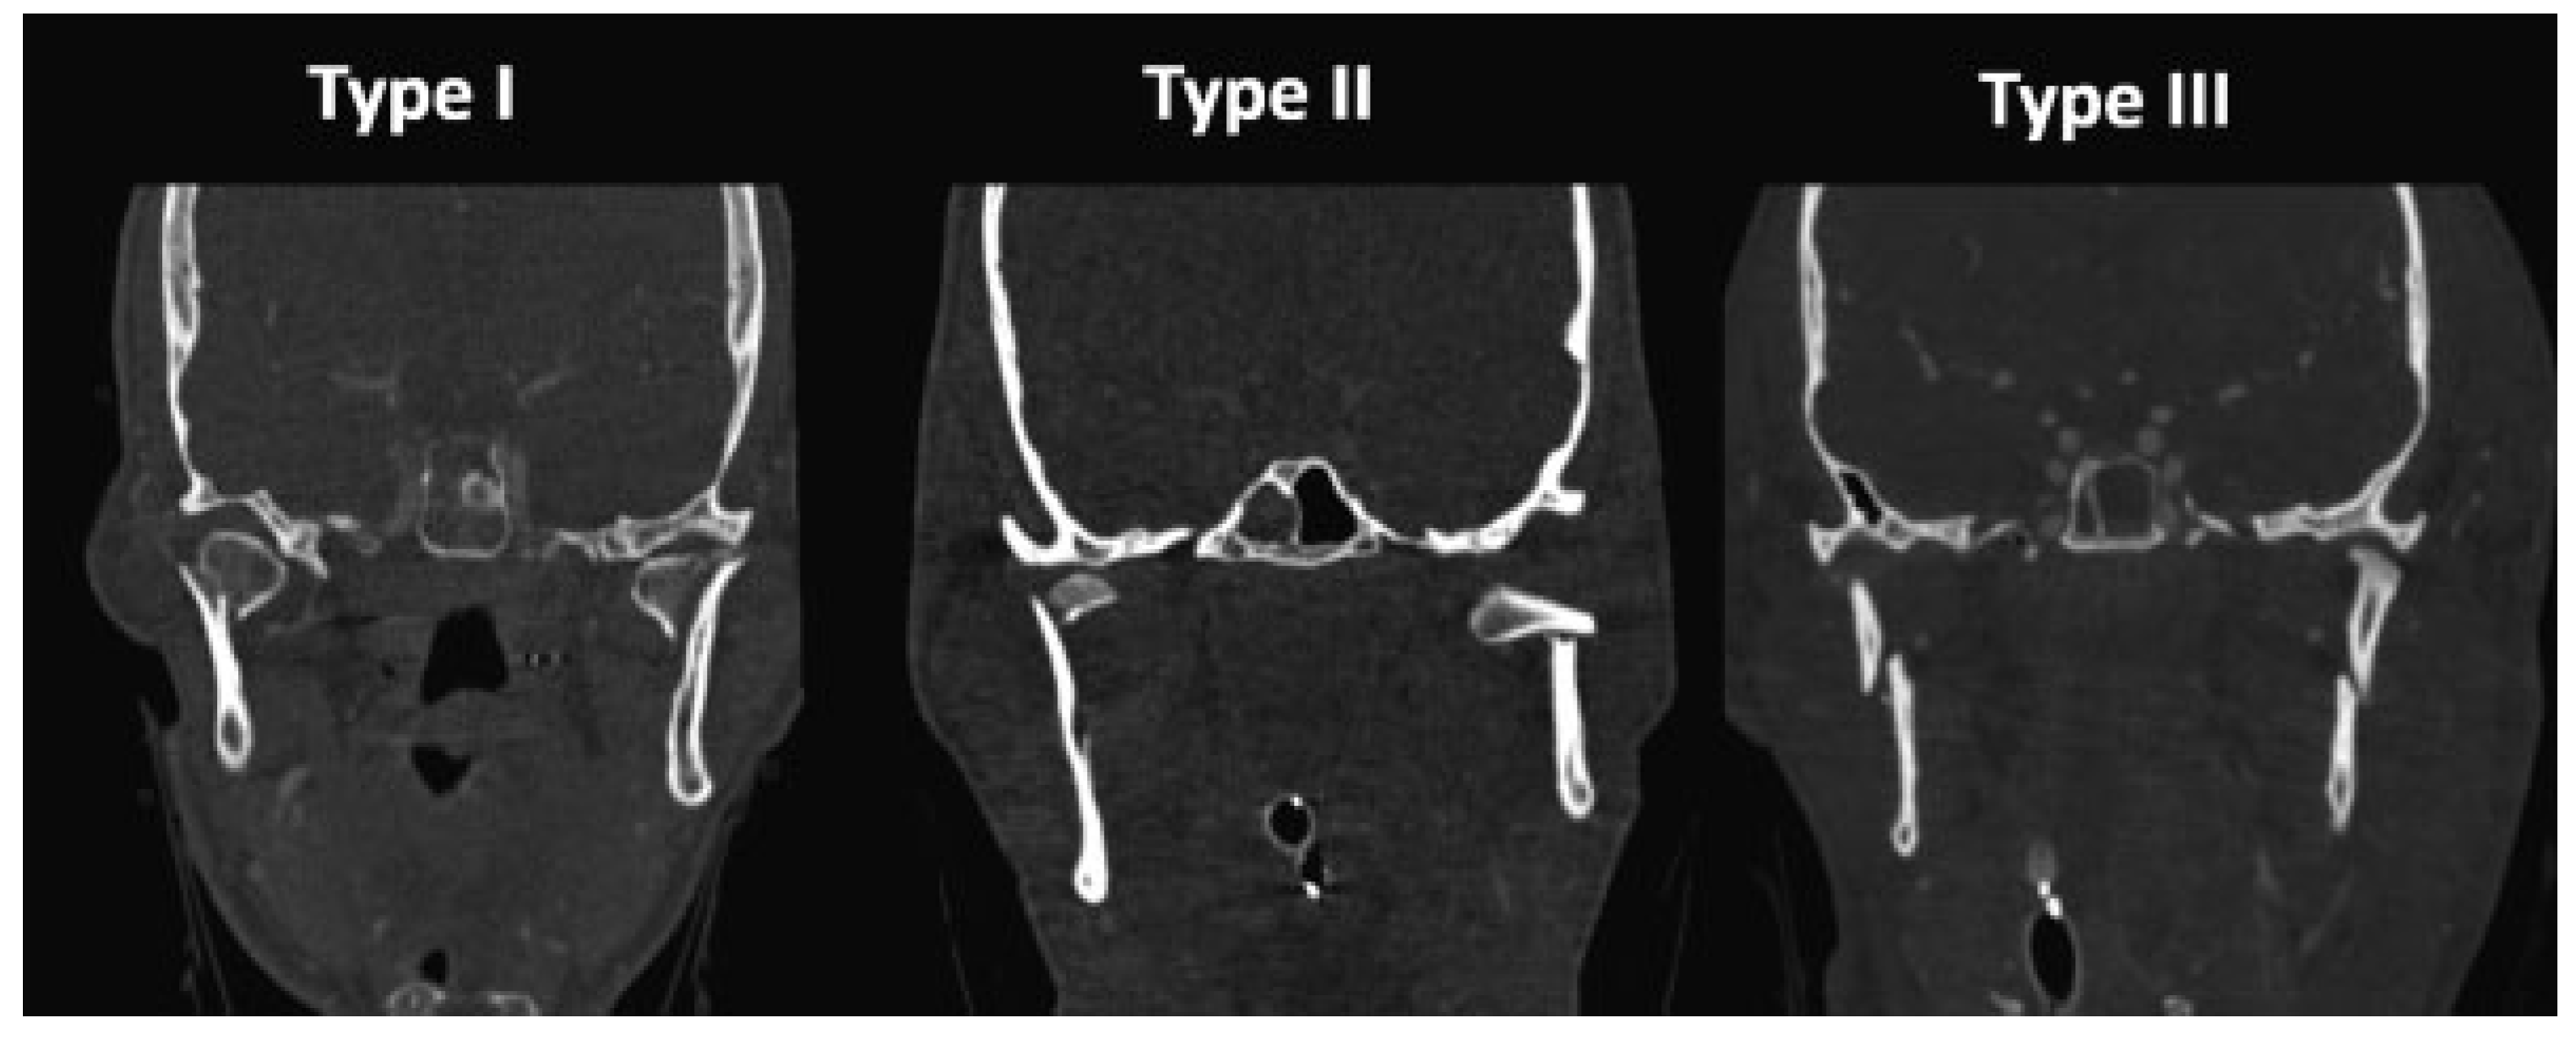

Case 2: Unilateral ORIF of Type II Injury

A 19-year-old man was involved in an ATV crash and pre- sented with left subcondylar, right condylar head (type II), and right parasymphyseal fractures (Figure 3). He underwent rigid fixation of the parasymphyseal fracture. The left subcondylar fracture was displaced medially and dislocated from the glenoid fossa; open reduction of this fracture was performed through a retromandibular approach and fixation was achieved with a 2.0-mm plate. The right condylar head injury was intracapsular and was managed with closed treatment. The patient was placed into IMF with guiding elastics immediately postsurgery. On subsequent follow-up, active and passive mouth opening exercises were initiated. At the 8-week follow-up, his MMO remained limited at 23 mm. Continued physical therapy was recommended, but the patient was then lost to follow-up.

Figure 3. Type II bilateral condylar injury managed with unilateral open reduction and internal fixation (ORIF). CT images of a patient with a right condylar head fracture, a displaced left subcondylar fracture with complete dislocation of the temporomandibular joint, and a right parasymphyseal fracture (above). Postoperative CT images after ORIF of right parasymphyseal and left subcondylar fractures and intermaxillary fixation (below).